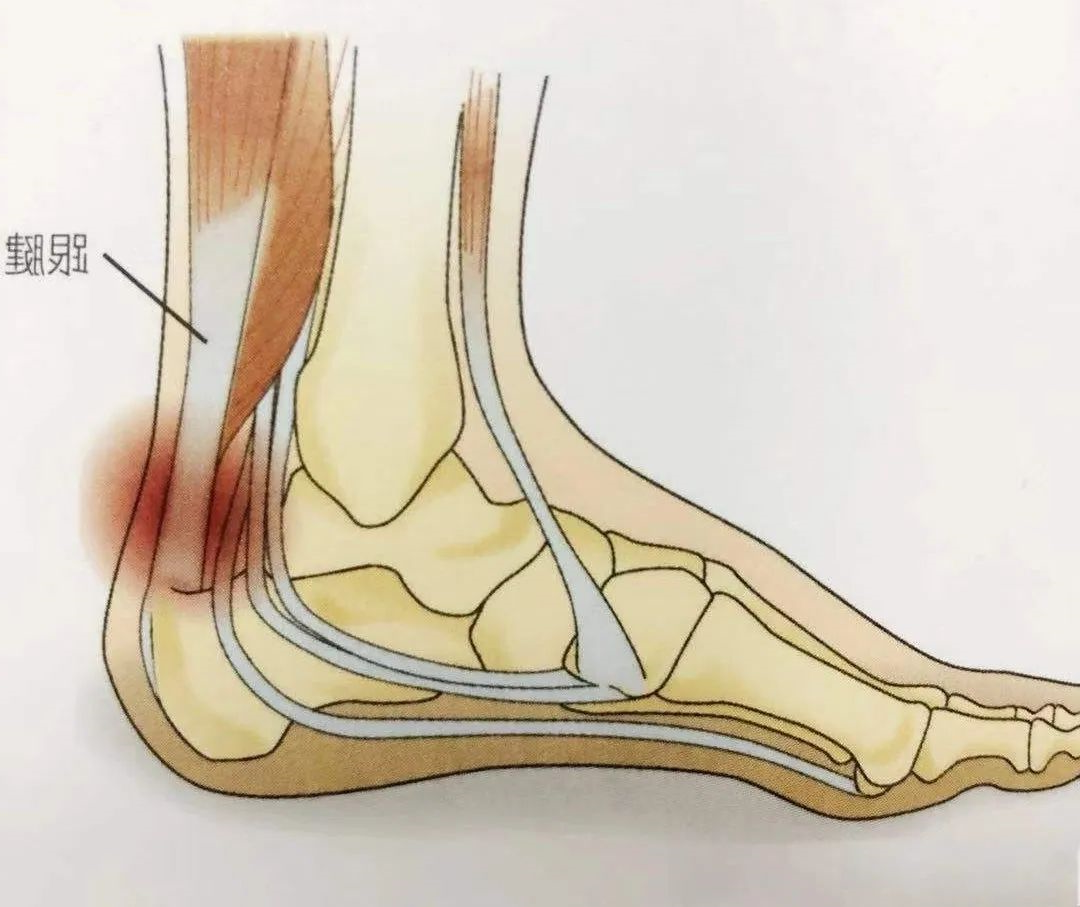

跟腱炎

跟腱炎主要是指跟腱及周围的腱膜在行走、跑跳等剧烈运动时遭受劳损,发生部分纤维撕裂、充血、水肿、变性,甚至钙化等,以局部疼痛,足跟不能着地,踝关节背伸疼痛加重等为主要表现的无菌炎症性疾病。ESWT治疗跟腱炎有效率为 70%~95%。